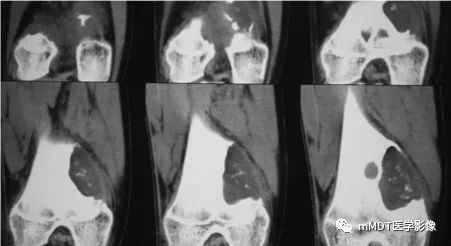

病史:15岁男性,右膝不适2年,行走及上楼时疼痛不明显。查体:右膝内侧膨隆,屈曲略受限,局部皮温正常,皮肤完整。影像资料如下:

CT冠状面软组织窗

CT见病变位于股骨远端干骺端,呈分叶状、偏心膨胀性生长,密度欠均匀,整体低于肌肉密度,部分区域密度接近水,其内可见点状、线状、弧形、圆形的高密度影,大部分边缘硬化,局部深侵蚀骨内膜,局部骨壳不完整。MR上,T1WI信号略低于肌肉,T2压脂呈现不均匀高信号,未见明确软骨小叶结构及纤维分隔,周围可见水肿。